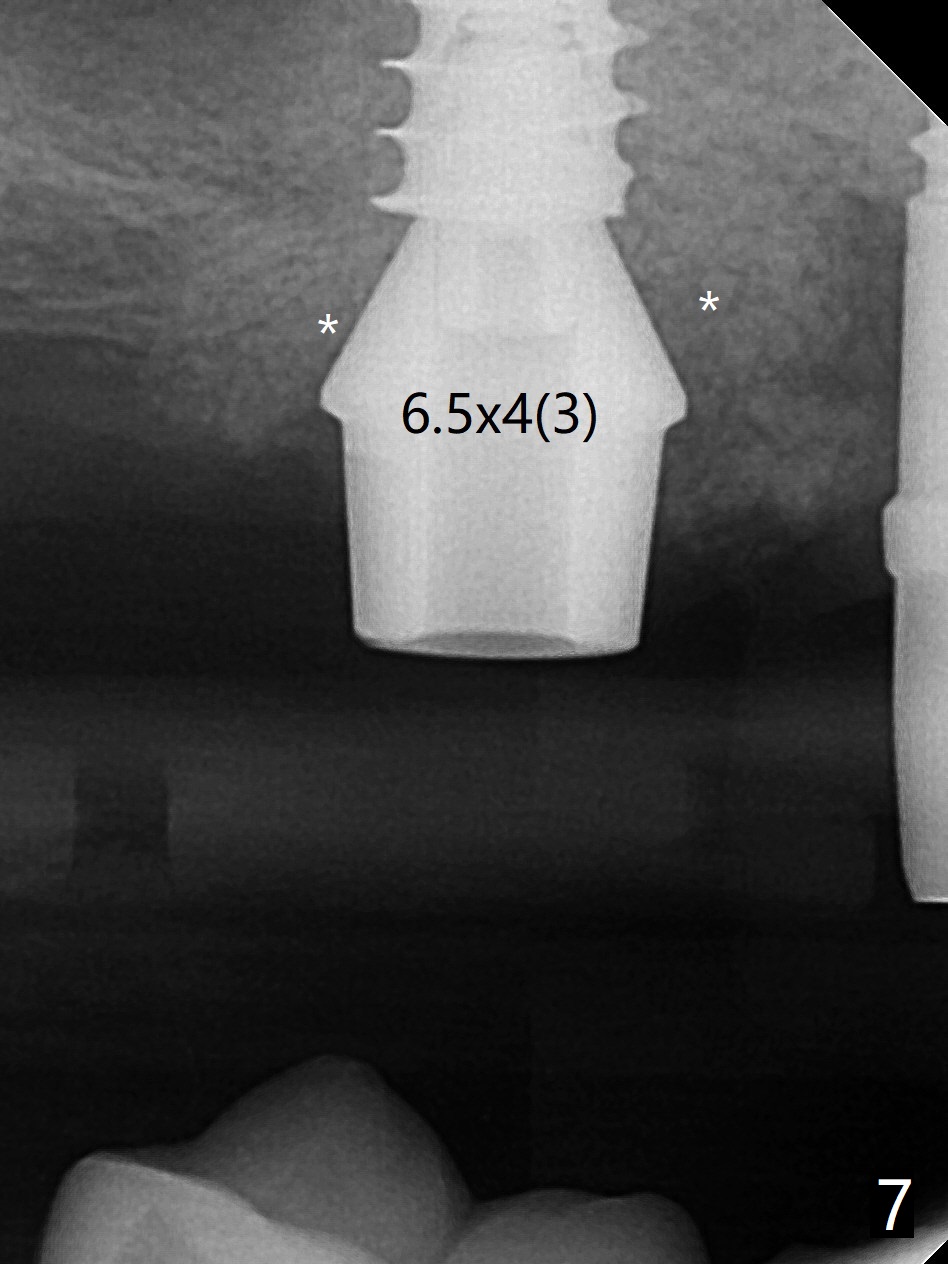

术前清晨复习3号牙窦底,中央是植骨(图一,二:*(皮质骨:密度高,质地可能软)),由于窦底斜坡,术前估计穿孔可能最先发生在远中,术中的确如此(图三:<(使用4毫米钻头后)),放置粘性骨粉(图四),利用导板(图五:G)和4x9毫米报废植体提升(*)。使用4.5毫米钻头,放置半张PRF膜,骨粉,5x7毫米植体以及修复基台,最后在后两者周围放置骨粉(图六,七:*(腭侧一个螺纹暴露)),覆盖1/2PRF膜,缝合,树脂敷料。